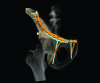

Methods: 7 patients (5 male and 2 female; median age 53 y (25 to 92 y)) with an acetabular fracture were prospectively included. Exclusion criterions were simple wall fractures, cases with anticipated surgical dislocation of the femoral head for joint debridement and accurate fracture reduction. According to the Letournel classification 4 cases had two column fractures, 2 cases had anterior column fractures and 1 case had a T-shaped fracture including a posterior wall fracture.The workflow included following steps: (1) Formation of a patient-specific bone model from preoperative computed tomography scans, (2) interactive virtual fracture reduction with visuo-haptic feedback, (3) virtual fracture fixation using common osteosynthesis implants and (4) measurement of implant position relative to landmarks. The surgeon manually contoured osteosynthesis plates preoperatively according to the virtually defined deformation. Screenshots including all measurements for the OR were available.The tool was validated comparing the preoperative planning and postoperative results by 3D-superimposition.

Results: Preoperative planning was feasible in all cases. In 6 of 7 cases superimposition of preoperative planning and postoperative follow-up CT showed a good to excellent correlation. In one case part of the procedure had to be changed due to impossibility of fracture reduction from an ilioinguinal approach. In 3 cases with osteopenic bone patient-specific prebent fixation plates were helpful in guiding fracture reduction. Additionally, anatomical landmark based measurements were helpful for intraoperative navigation.